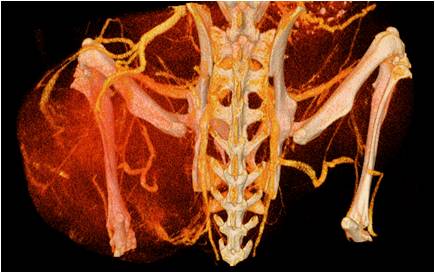

心血管

胸部和心血管的層析成像                                       胸部和心血管的3D圖像